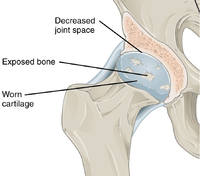

In a healthy joint, the ends of bones are encased in smooth cartilage. Together, they are protected by a joint capsule lined with a synovial membrane that produces synovial fluid. The capsule and fluid protect the cartilage, muscles, and connective tissues.

With osteoarthritis, the cartilage becomes worn away. Spurs grow out from the edge of the bone, and synovial fluid increases. Altogether, the joint feels stiff and sore.